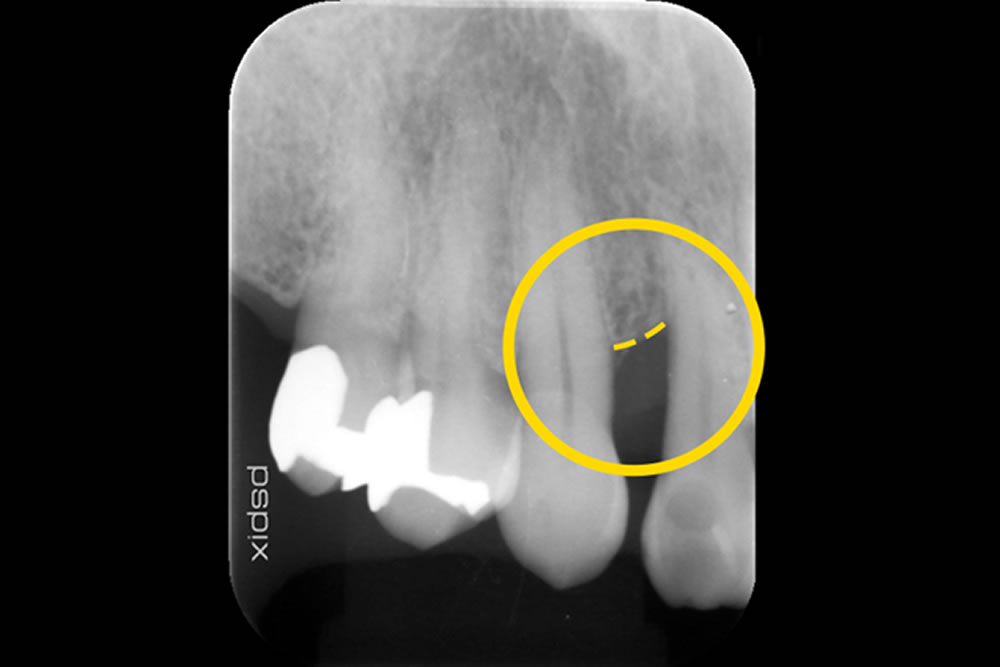

MINSTによって重度歯周病の症状を改善した症例

| 治療内容 | ・低侵襲非外科治療(MINST)「歯茎を切らない歯周病治療」 ・レーザーペリオ治療 |